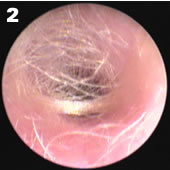

小婴儿耳道有丰富的绒毛,有时会影响窥视

如果发现耳道耵聍持续大块堵塞不能掉出,就需要面诊小儿耳鼻喉医生协助处理。

① 请另一个人固定娃的头部和身体;

② 拉直耳道、扩张耳道口。用拇指、中指向后下轻轻拉耳垂,食指向反方向按压;

③ 推开耳屏前皮肤,露出耳道口;

④ 用一支直光远射小电筒(手机闪光灯是不行的),向耳道内垂直照射,这样就能看到耳屎了。

PS:如果看不到,可能是耳道没拉直,或者没选对光源,光是散的;或者,小婴儿耳道绒毛遮挡,这种情况需要电耳镜才能更好的看见。